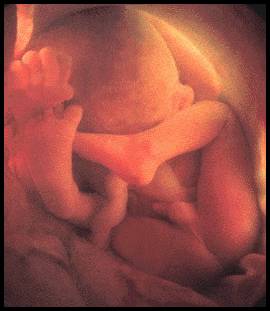

ภาพทารกในครรภ์เมื่ออายุได้ 5 เดือน

การตั้งครรภ์เดือนที่ 5 ผ่านมา 4 เดือนอาการของคุณแม่เริ่มแพ้ท้องลดลง แต่จะมีอาการอื่นๆ ที่ทรมานยิ่งกว่าเพิ่มมากขึ้น เริ่มตั้งแต่ ปวดหัว ร่างกายอ่อนเพลีย ท้องผูก ทารกในท้องที่โตขึ้น ส่งผลให้ท้องมีขนาดใหญ่ขึ้น ช่วงนี้เรียกได้ว่าคุณแม่ทั้งหลายต้องยอมหมดสวยเพื่อเราเลย เพราะไม่ใช่แค่ท้องที่ใหญ่ขึ้นเท่านั้น ต้นขาและน่องก็ใหญ่ขึ้นด้วย นอกจากนี้เม็ดสีของร่างกายก็จะเปลี่ยนแปลงเป็นสีเข้ม ทำให้บริเวณท้อง หน้าอก หรือใบหน้าบางจุดเข้มขึ้น ตามที่เคยได้ยินกันมาว่า เวลาท้องจะมีฝ้าหรือกระนั่นเอง ส่วนคุณลูกอย่างเราๆ ก็โตขึ้นตามลำดับ สามารถแยกเพศได้แล้ว แขนขา กระดูกมีความแข็งแรง ทำให้มีการเคลื่อนไหวมากขึ้น ในตอนนี้มือไม้เราเริ่มจะไม่อยู่สุข (แค่อย่าไปบีบสายสะดือของตัวเองก็พอ ฮ่าๆ) ช่วงนี้แม่อาจจะเจ็บท้องเพราะการเคลื่อนไหวของเราอยู่บ่อยครั้ง นอกจากนี้ในเดือนที่ 5 เราสามารถจำเสียงของคุณแม่ได้แล้วด้วยนะ และอาจจะมีการสนองตอบเสียงภายนอกด้วย เช่น มีการเคลื่อนไหวเมื่อได้ยินเสียงเพลง (น่ารักอ่ะ^^)